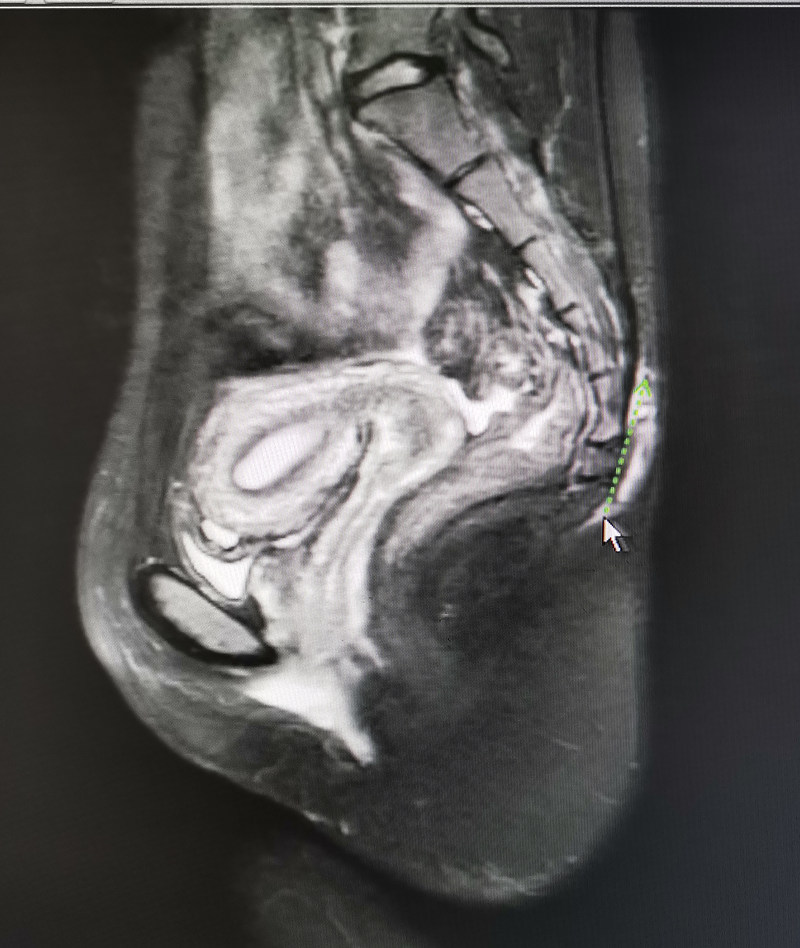

一20岁患者因反复骶尾部红肿溢脓一年余,曾在外院多次就医均效果不佳,于2020年7月10日来县人民医院急诊科就诊。谢义强主任接诊后,经详细询问病史,仔细体格检查,并结合盆底部磁共振扫描,确诊为藏毛窦,建议住院手术治疗。传统手术方式为:根治性藏毛窦切除,但切口必须敞开,需经历三个月左右清洁换药后,创面才能缓慢愈合。目前国内最新手术方式为彻底切除窦道+带蒂复合组织皮瓣转移术,一期缝合伤口。该术式我院尚未开展,谢主任将病人收住后,积极完善术前准备,精心设计手术方案,在六安市人民医院专家指导下,于7月11日为患者行“骶尾部根治性藏毛窦切除+带蒂复合组织皮瓣转移术”。手术历时1小时,手术经过顺利,术后一般2周即可痊愈出院。

核磁共振检查,藏毛窦位置(绿色箭头)